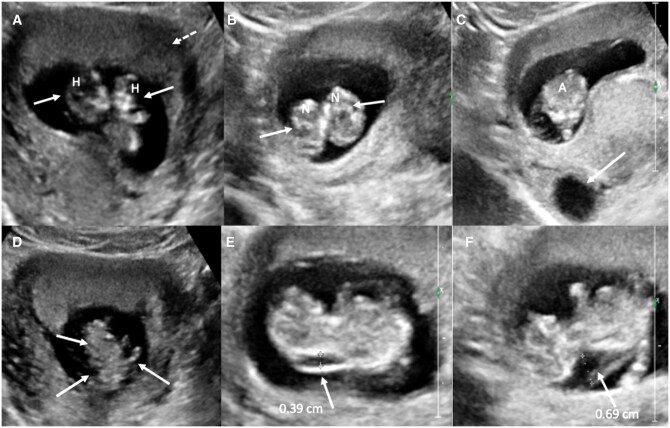

Conjoined twins, or Siamese twins as they are commonly called, are a rare and extreme form of monochorionic twinning. Imaging plays an essential role in the diagnosis and follow-up of conjoined twins. While ultrasound is often the screening modality of choice, MRI is carried out for better anatomical delineation and further characterization as and when necessary. We present a unique case of first trimester thoraco-omphalopagus conjoined twins with cystic hygroma who were comprehensively evaluated with sonography and MRI with imaging findings confirmed post-pregnancy termination. The case stresses upon the utility of advanced imaging techniques including foetal MRI that immensely contribute towards a reliable diagnosis.